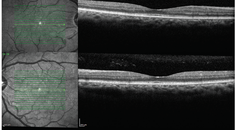

From a surgical perspective, patients may only be seen once when they come in for a surgical evaluation, which includes preoperative measurements for cataract surgery and critical tests for dry eye. For cases like this, we use a protocol algorithm created by the American Society of Cataract and Refractive Surgery (ASCRS).2 The protocol begins with a subjective questionnaire that is very helpful for identifying symptoms indicative of dry eye disease in our surgical patients. Next, we conduct some objective testing, such as osmolarity testing, using the TearLab Osmolarity System (Figure 1). We conduct MMP-9 testing, which is also outlined in the ASCRS protocol. Both of these tests are deemed “essential” preoperative diagnostic tests by the ASCRS.2 If any one of the tests are abnormal, that triggers the next stage of observation as we become suspicious that the patient has some form of ocular surface disease.

For example, if a minimally symptomatic patient comes in presenting with slight inferior staining and an osmolarity score of 330 mOsm/L, we would consider that more than a standard deviation from the norm, indicating the patient may have a problem with his or her tear homeostasis. In general, if a patient’s inter-eye difference is 8 mOsm/L or greater, or osmolarity are over 308 mOsm/L, then it is time to investigate further before doing anything else.